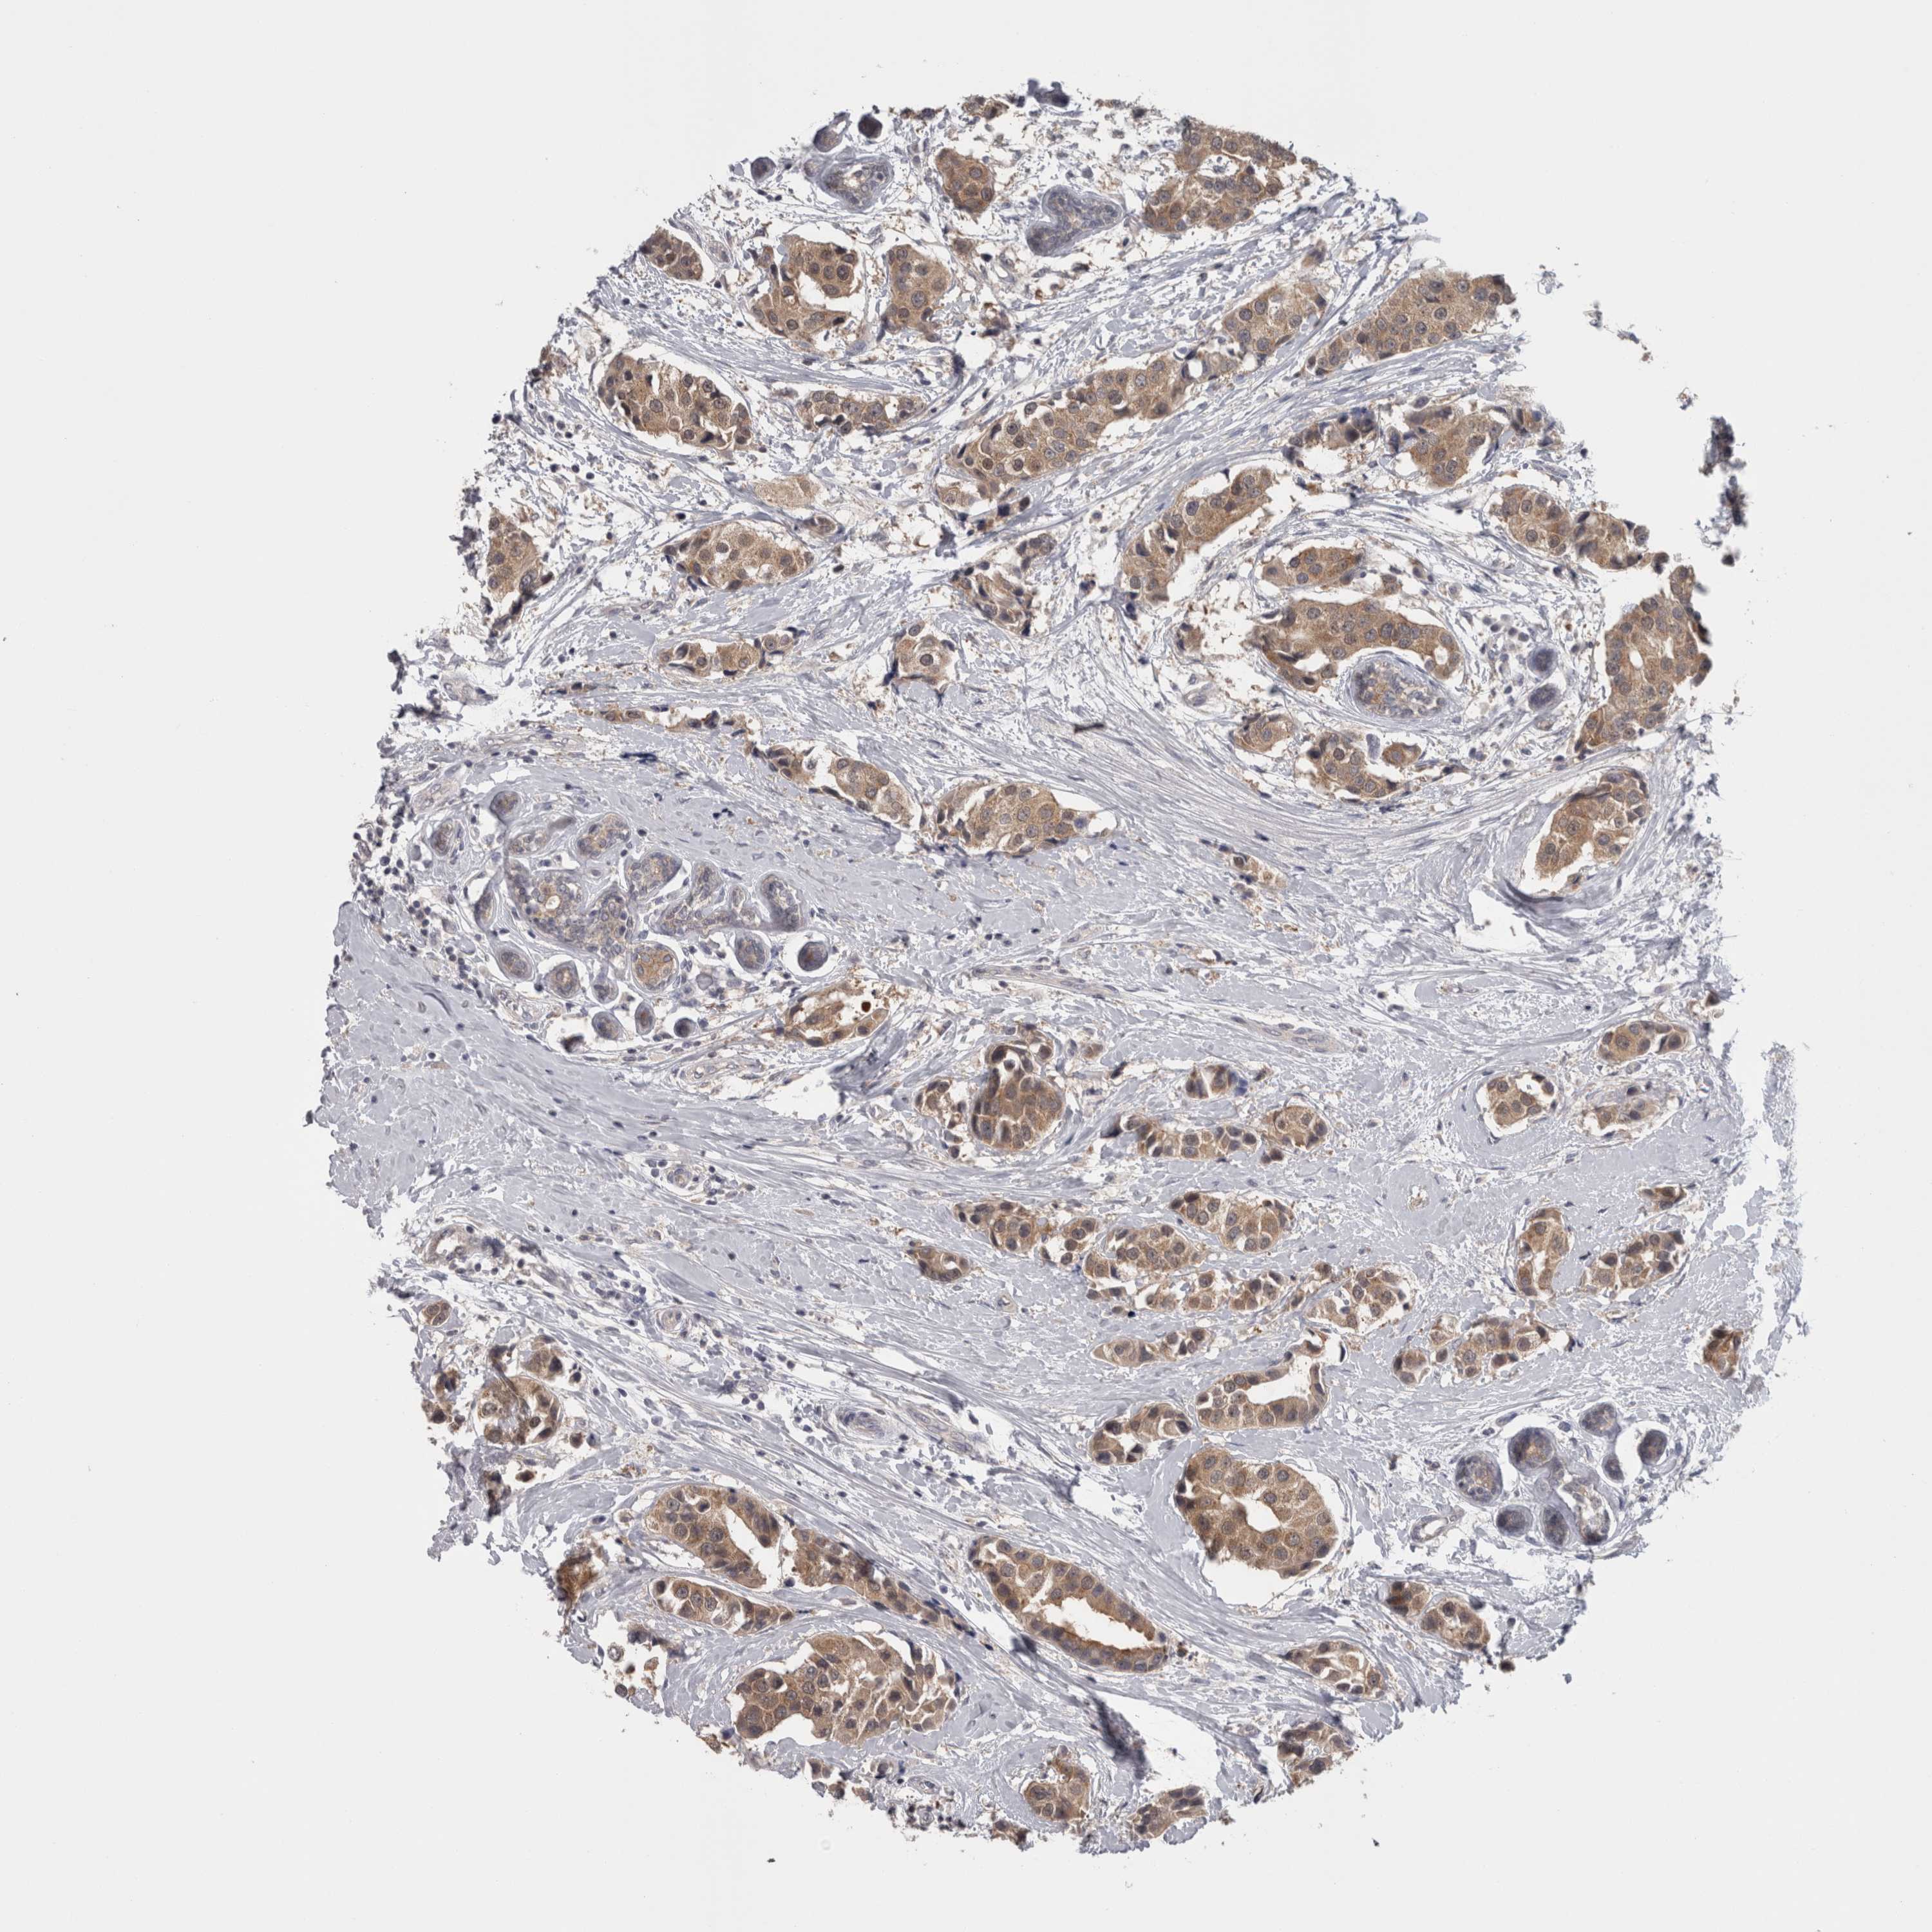

CANCER BREAST CANCER Show tissue menu

BRCA TCGA BRCA VALIDATION PROTEIN EXPRESSION